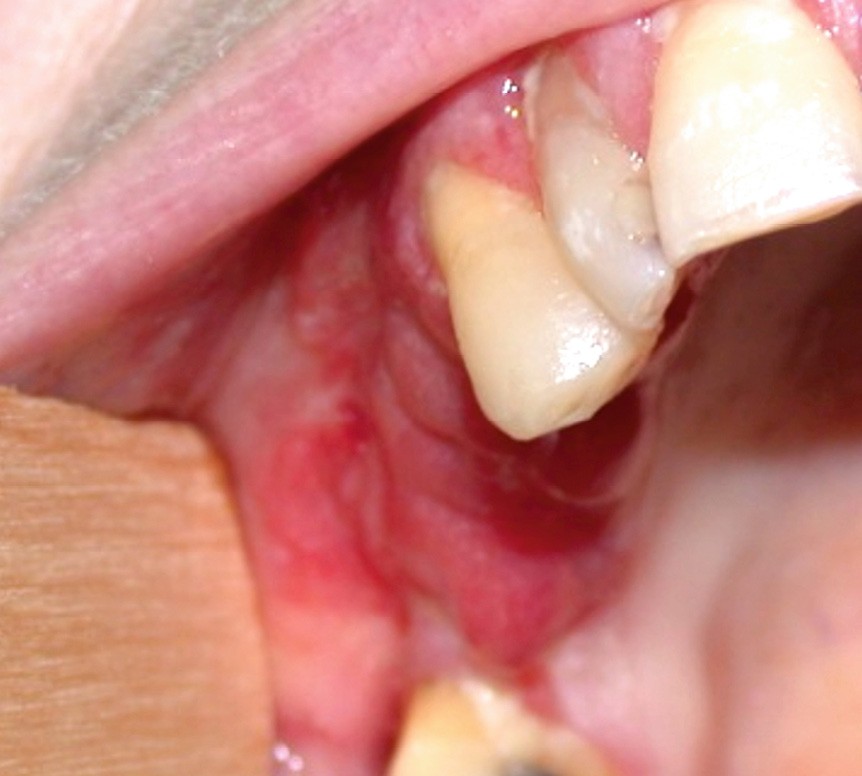

Érythroplasie isolée : elle se caractérise par une macule (fig. 2a), une plage (fig. 2b), une plaque (fig. 2c) limitée sans cause évidente.